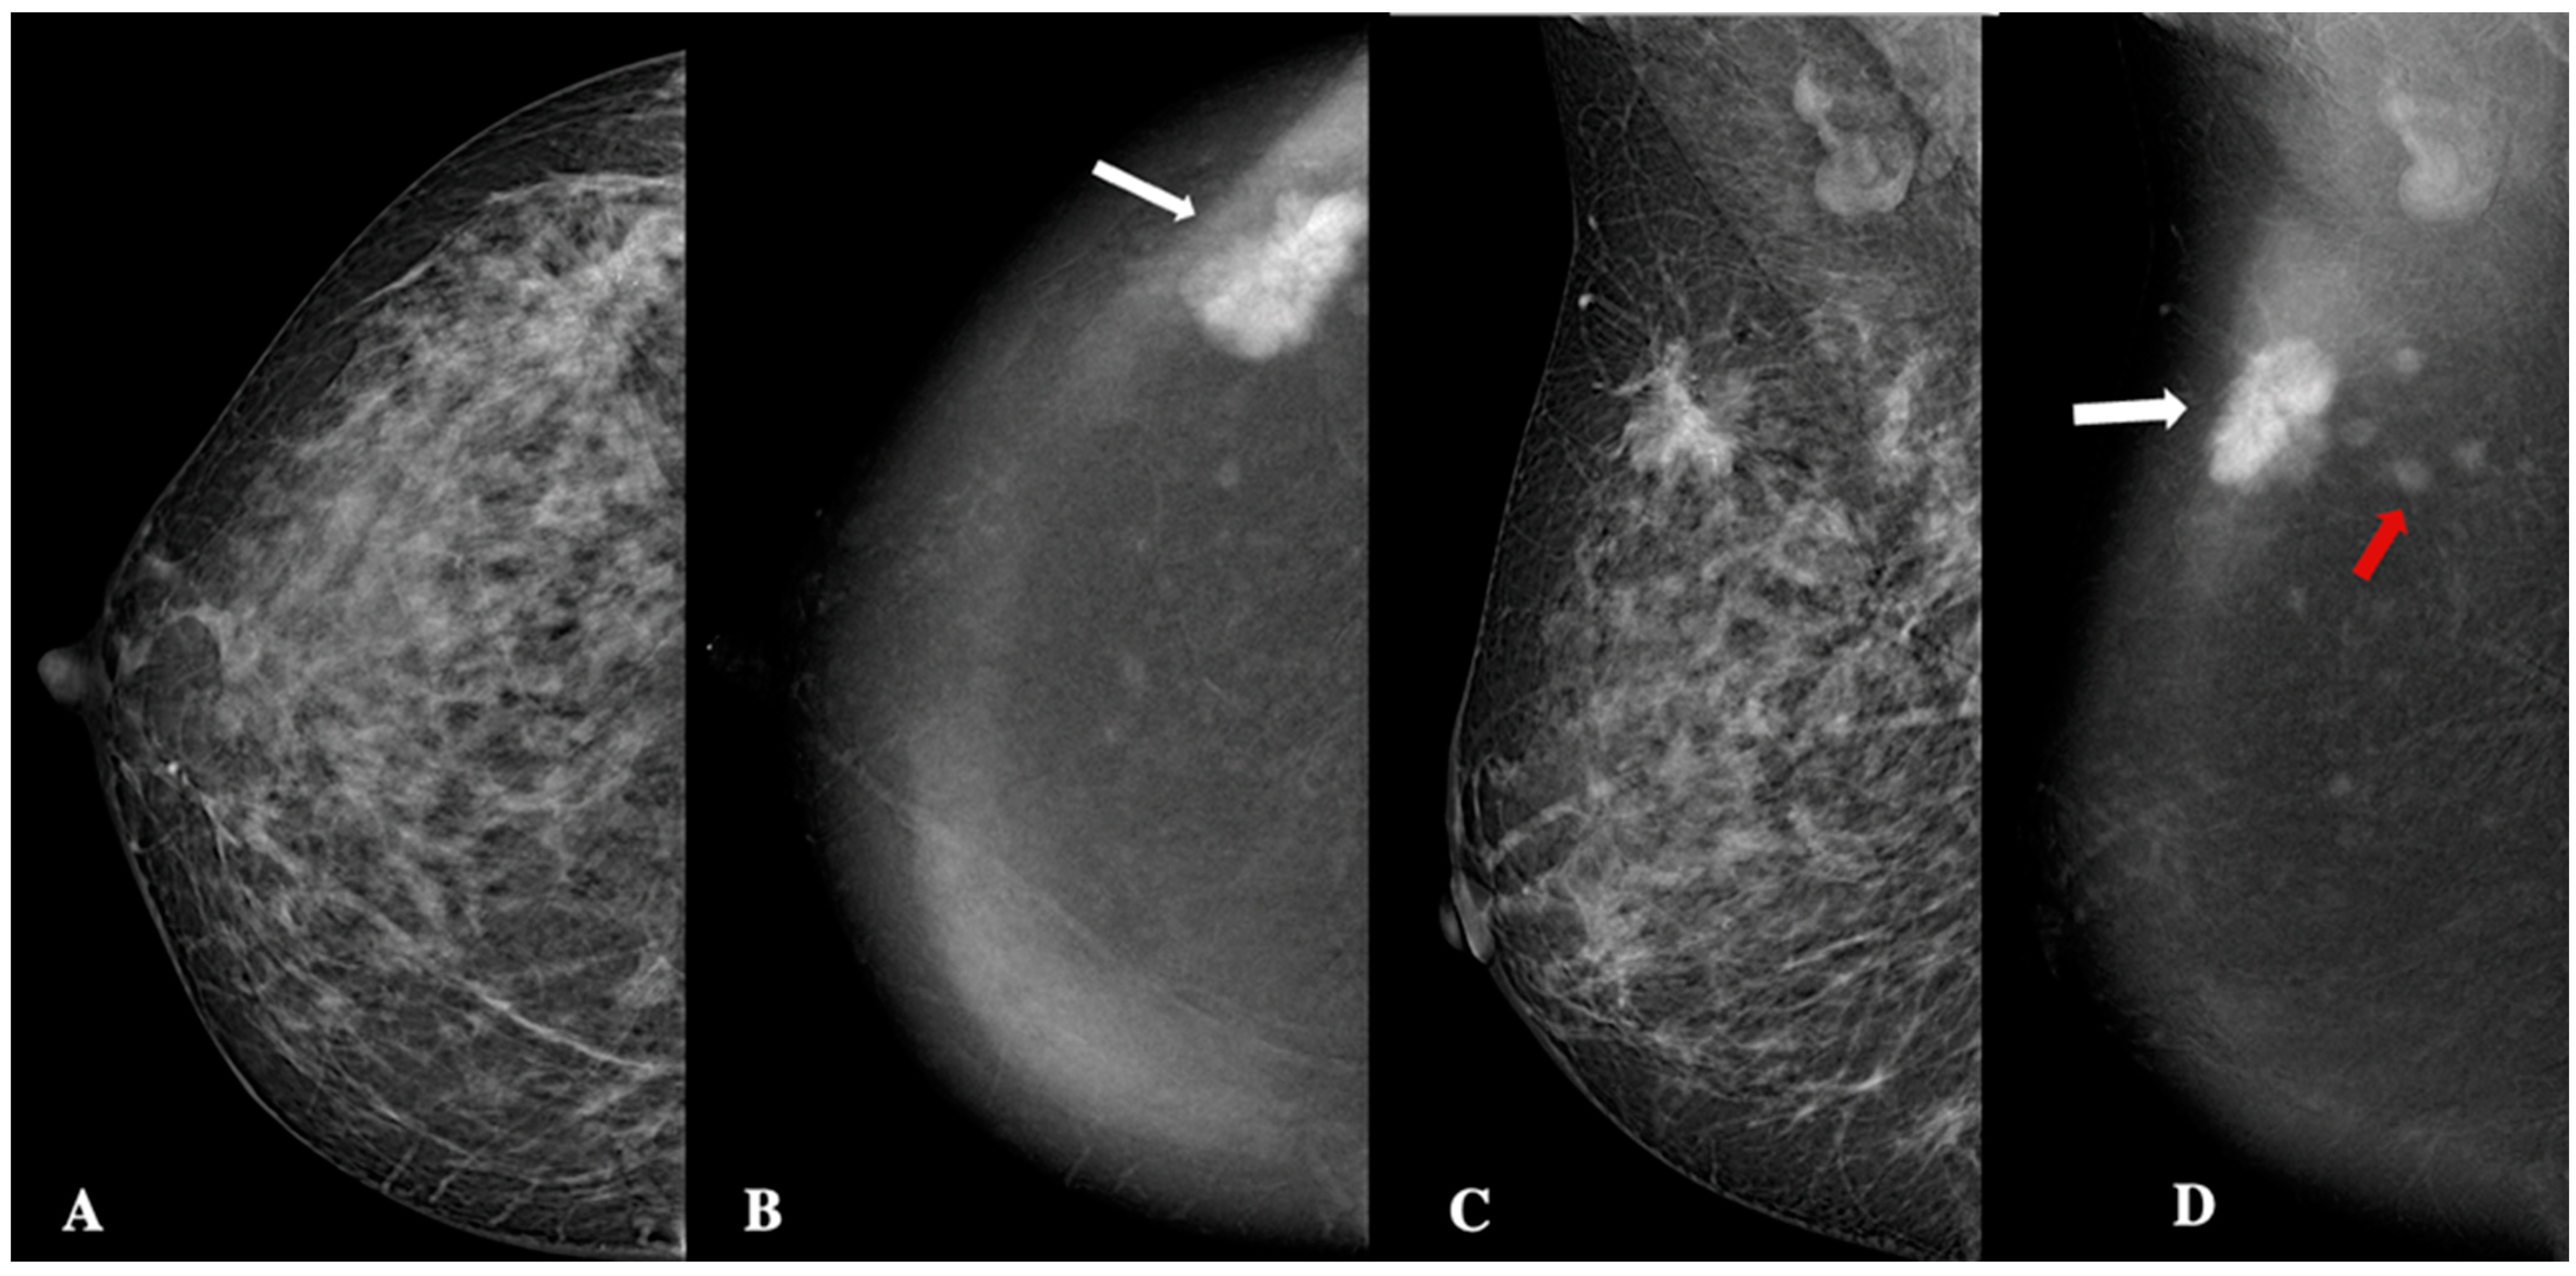

| Microcalcifications | Present (n, %)/absent (n, %) | 11 (22%)/39 (78%) |

| Architectural distorsion | Present (n, %)/absent (n, %) | 34 (68%)/16 (32%) |

| Lesion shape | Oval (n, %)/round (n, %)/irregular (n,%) | 31 (62%)/9 (18%)/10 (20%) |

| Lesion margins | NC (n, %)/C (n, %) | 7 (14%)/43 (86%) |

| Lesion internal enhancement | Homogeneous (n, %) | 8 (16%) |

| Heterogeneous (n, %) | 37 (74%) | |

| Rim enhancement (n, %) | 5 (10%) | |

| Lesion enhancement conspicuity | Low (n, %) | 25 (50%) |

| Moderate (n, %) | 10 (20%) | |

| High (n, %) | 15 (30%) | |